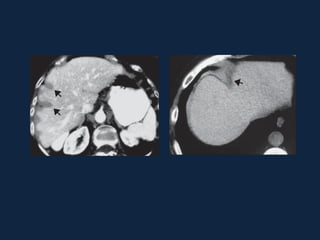

► s/c: Massa esférica, iso ou hipodensa (devido ao conteúdo lipídico).

Hemorragia: áreas hiperatenuantes intra-tumorais, parenquimatosas

ou subcapsulares.

Pode haver gordura ou calcificações.

► c/c:

– Fase Arterial: Realce intenso (< q na HNF) e heterogêneo

– Fase Portal: Diminuição da atenuação e da heterogeneidade do realce.

– Fase Tardia: Isodenso ao parênquima. Realce não persiste.

Adenoma Hepático

 Fase art.    Fase portal    Fase tardia

 S/C                Fase arterial

 Fase portal        Fase tardia